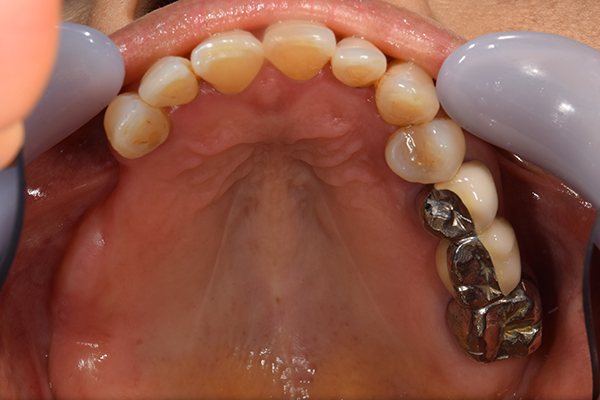

ケース1(自費の部分入れ歯)

前歯が折れて当院にいらっしゃいました。 過去に下の入れ歯を作ったが、合わなくなってずっと入れ歯をいれていらっしゃらない患者様でした。 これは奥歯で噛むことができないため、前歯で噛むことを繰り返したために、負担に耐えられなくなった前歯が折れてかぶせ物ごと 外れてしまったのだと考えられます。 痛くない、違和感の少ない、下の入れ歯を作ることがこの方のゴールであると考えられました。

シリコンで精密な型取りを行いました。

噛み合わせチェックです。 奥歯でしっかりものが噛める様に高さを決めていきました。

金属を使用して、薄く違和感が少ない入れ歯が完成しました。 また、見た目にも気を使い、バネが見えにくい様な構造にしました。

入れ歯をお口の中にいれた状態です。前歯もMTMといって、歯を少し引っ張り出す処置を行なったことで、しっかり残せて、またかぶせ物をしました。

年齢 70歳・女性

主訴 前歯が取れた

治療期間 8ヶ月

治療費 .MTM:110,000円

.ファイバーコア:16,500円

.E-maxクラウン:110,000円

.義歯:660,000円

治療方針 長年使ってきた義歯の人工歯が磨耗し、臼歯部での咬合がすくなくなり、前歯部での接触が強くなったことで生じた前歯の破折なので、義歯も作り変える必要がある。

治療内容 前歯部MTMと同時に審美面の回復。

MTM中に義歯の作成も同時に行う。

最終的に義歯と前歯のクラウンを同時にいれる。

義歯は下顎で、しっかり噛めること、違和感の少ないものという希望があったため、なるべく入れ歯を薄く作成するために金属をしようした義歯とした。

また、見た目もあまり義歯が目立たない様に、バネの部分を見えにくいように作成した。

特記事項 歯にもともと入っていた金属の種類によっては、歯自体の変色を治療で変えられないこともある。 義歯は作ってから痛みがでることがありますが、それは調整を行うことで痛くなくすることができます。